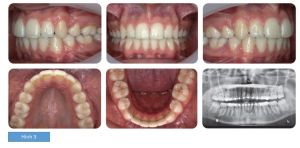

Bệnh nhân nữ 16 tuổi, băn khoăn về khe hở giữa các răng. Bệnh nhân bị sai lệch khớp cắn hạng II tiểu loại I trên nền xương loại II với kích thước dọc giảm, phức tạp bởi độ cắn chìa lớn (8mm), chen chúc cả 2 cung răng và hô 2 hàm (hình 1)